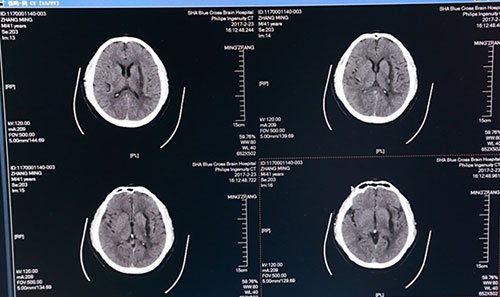

術(shù)后一周頭顱CT:血腫術(shù)后改變,血腫清除干凈

全腦血管造影(DSA)圖像:紅圈內(nèi)為出血部位,血管未見異常

術(shù)后第二日,復(fù)查頭顱CT示:左側(cè)基底節(jié)區(qū)血腫已基本清除干凈,術(shù)后一周再次復(fù)查頭顱CT示:左側(cè)基底節(jié)區(qū)血腫術(shù)后改變,血腫已基本清除,蛛網(wǎng)膜下腔滲出較前減少,金屬引流管撤除;術(shù)后一月復(fù)查全腦血管造影(DSA),出血點血管未見異常,排除腦動脈瘤破裂出血可能。目前患者精神奕奕,正在積極接受康復(fù)綜合治療,不日即可出院,回歸正常生活。